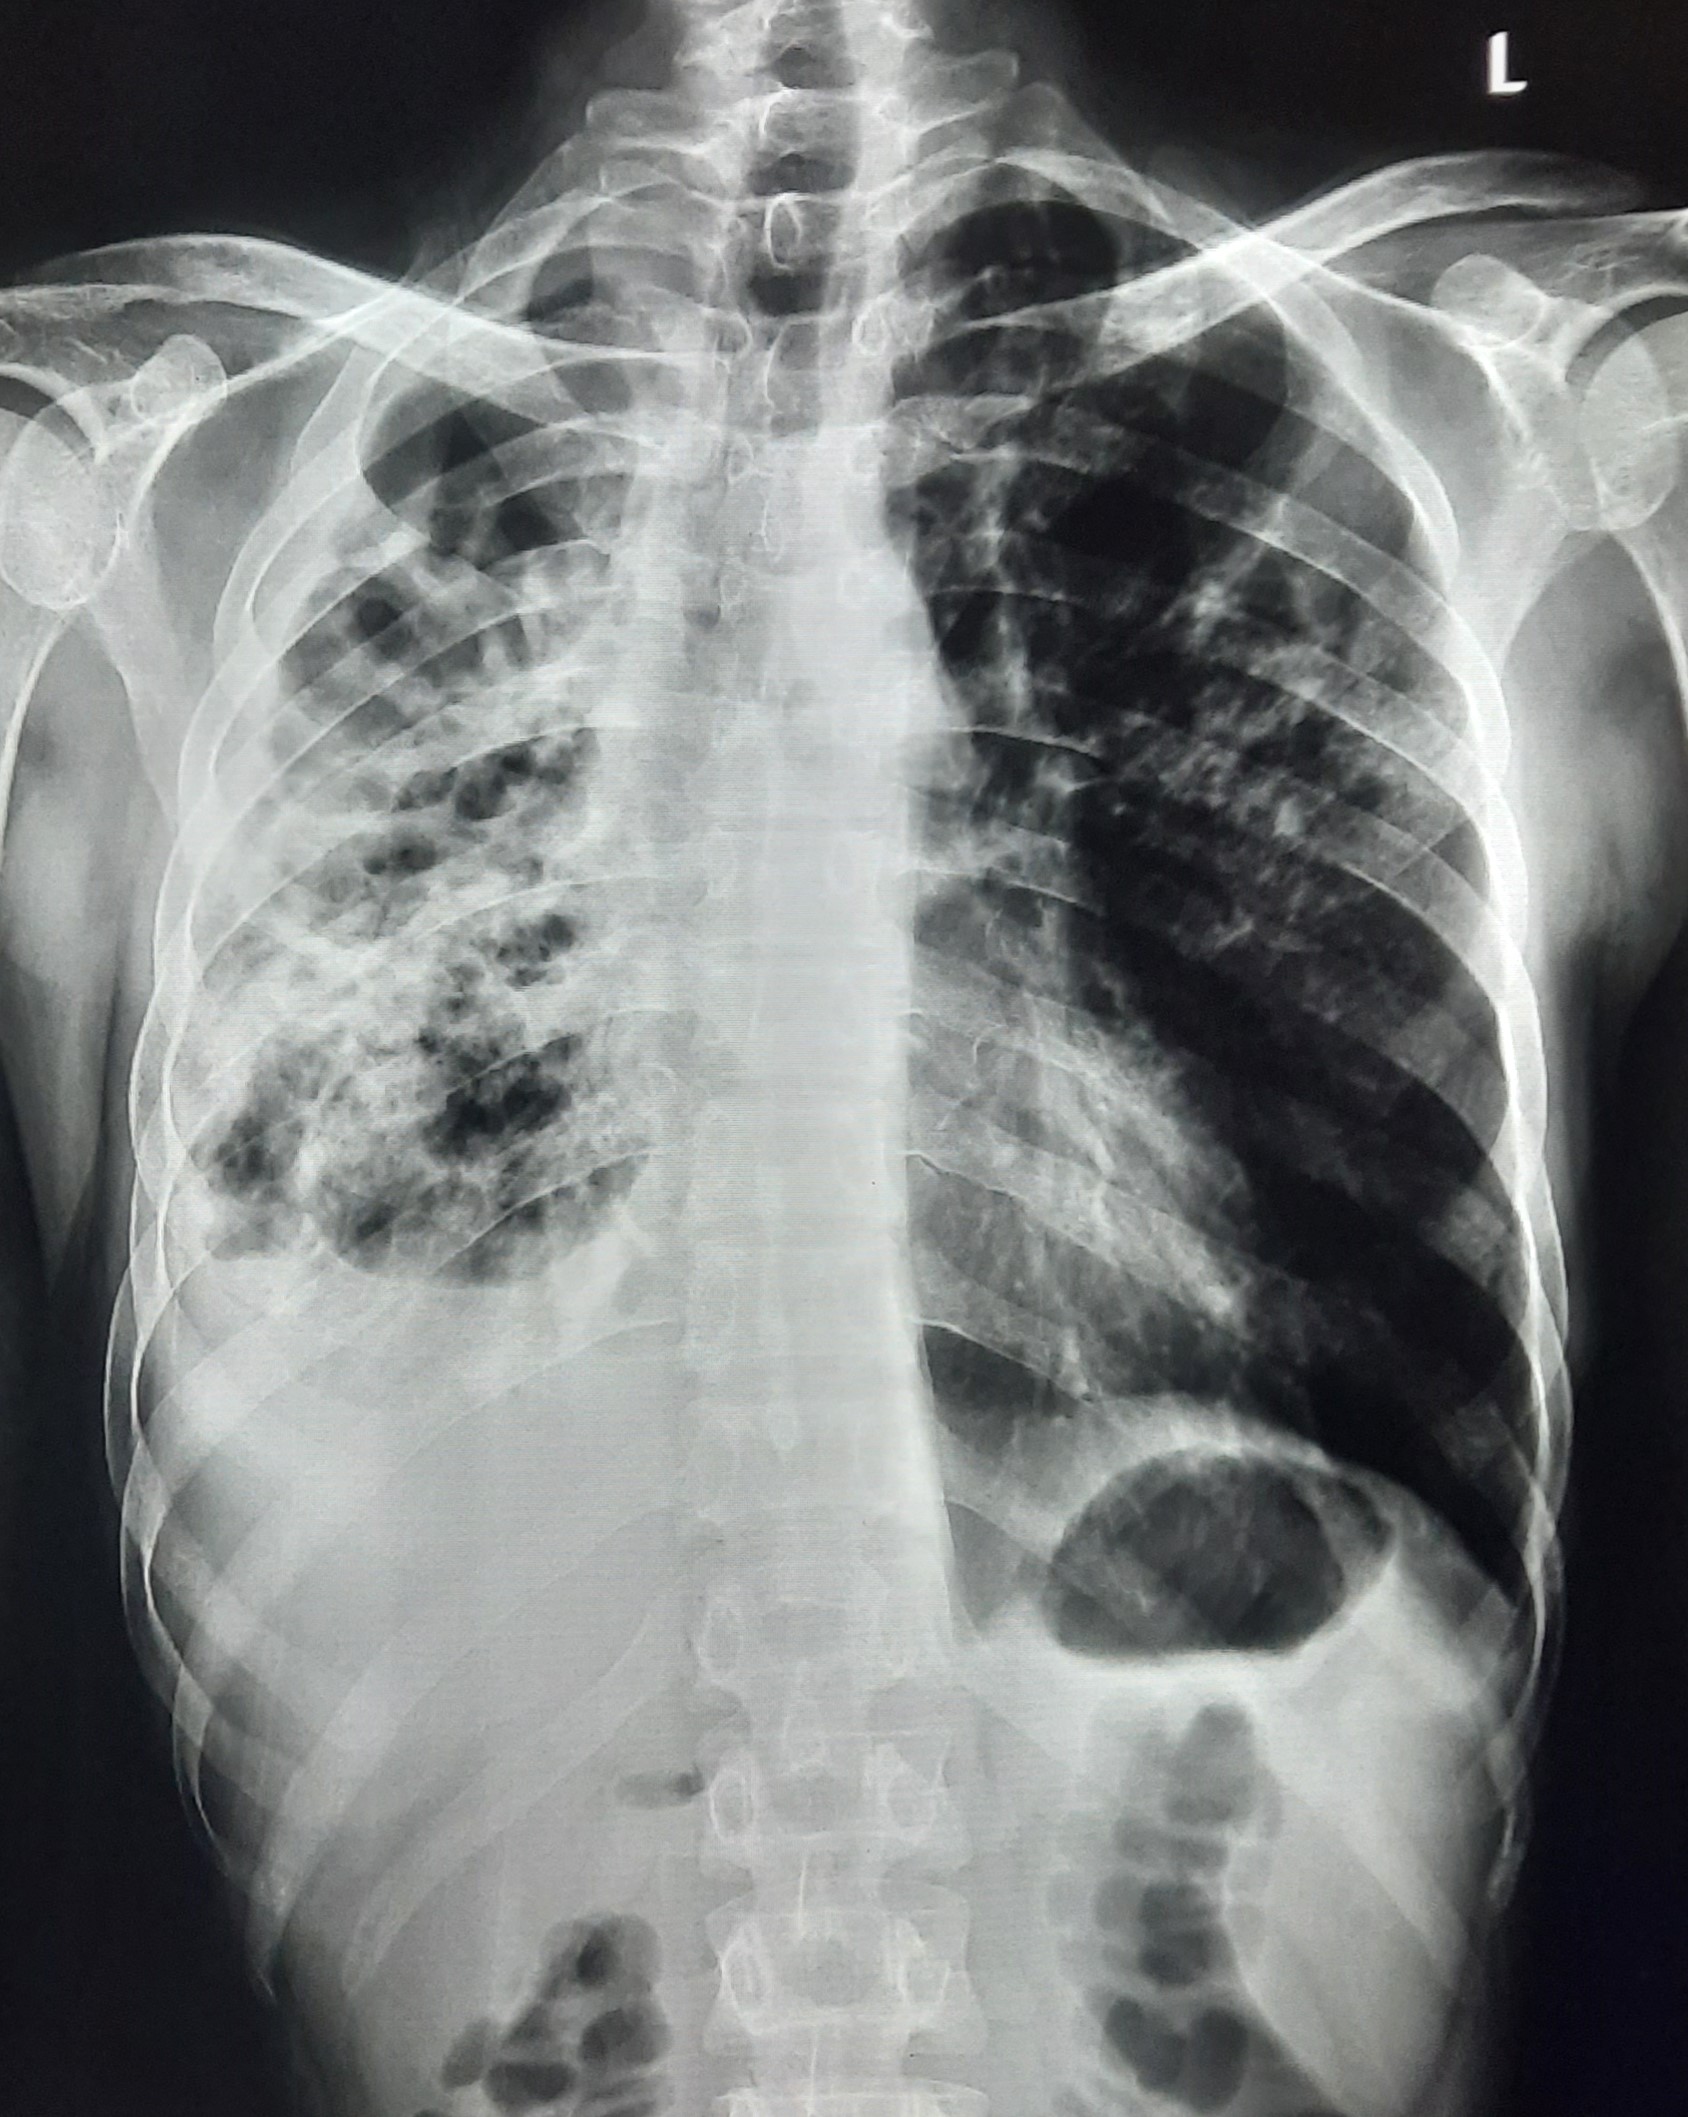

| 132 | IGGMC, Nagpur, Nagpur | P2 | 29-4340 | Ritesh Chaudhary | Consent taken on Paper | 30 Yrs. |

Provisional Diag : Post TB Sequelae

Final Diag : Post TB sequalae With Fibro Cavitary Changes |

Post TB Sequelae | Bilateral Upper Zone Fibro Cavitary Changes With Right Upper Zone Fungal Ball With Bilateral Haziness With Tenting Of Diaphragm | Abnormality visible on x-ray |